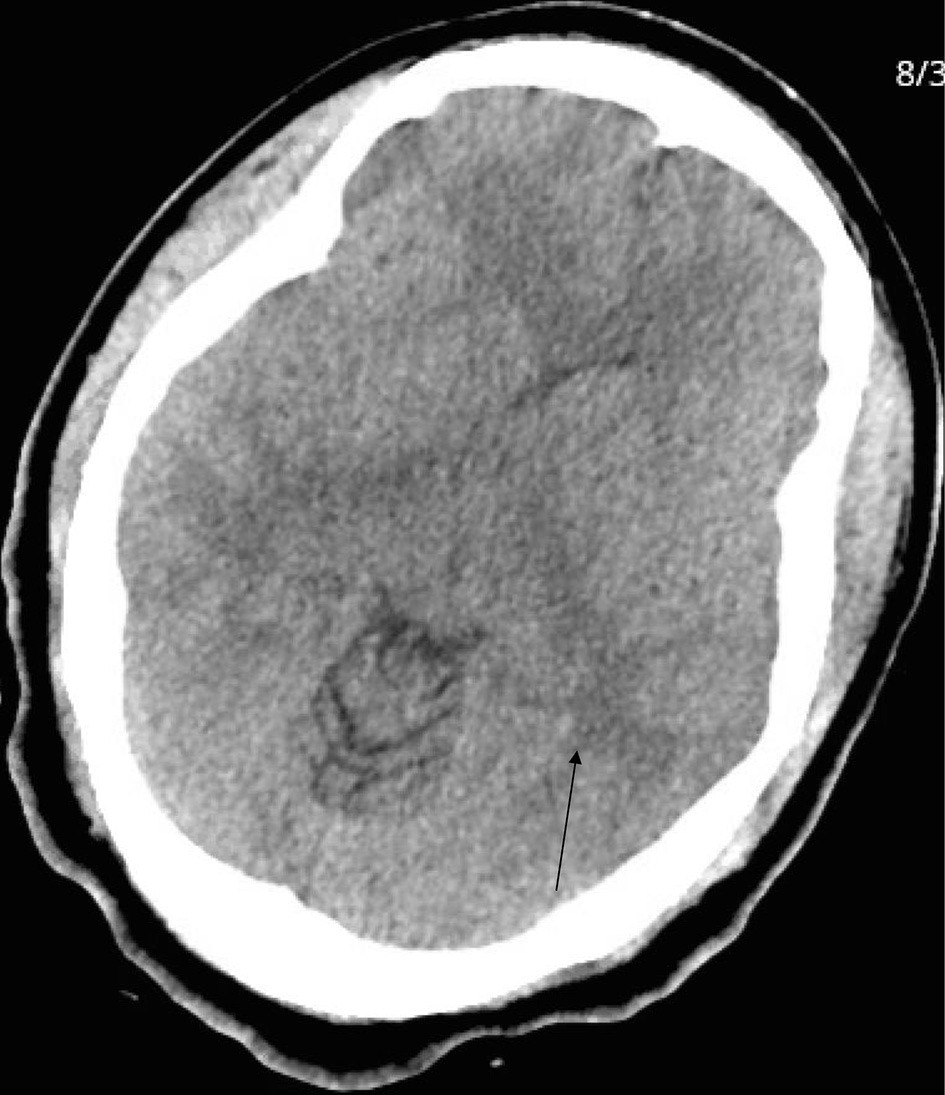

Patient continued to complain of headache, as reported in her ROS, and CT of head was performed (Fig. 2). It showed confluent white matter hypodensity within the vertex and posterior parieto-occipital region, consistent with posterior reversible encephalopathy syndrome (PRES).

![]() Click for large image | Figure 2. Head computed tomography. Arrow indicates confluent white matter hypodensity within the vertex and posterior parieto-occipital region, consistent with posterior reversible encephalopathy syndrome (PRES). |